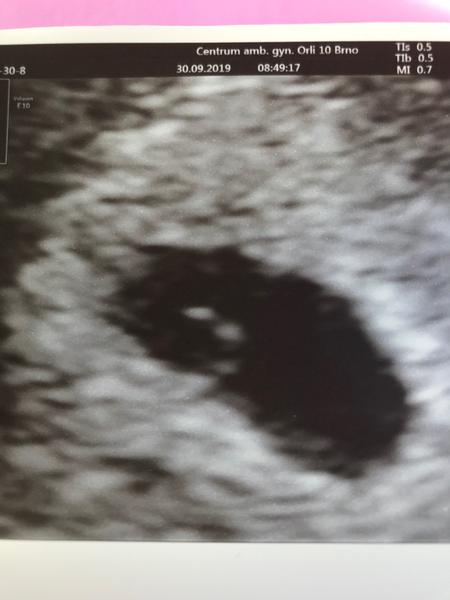

Ahoj,tak dnes kontrolni ultrazvuk...Mudr. Mardesicova byla nadsena,ja zase tolik ne...vypada to tak na 8-10 folikulu,odber v patek.Pane boze,prosim,at to vyjde🙂Uz bychom si to zaslouzili...